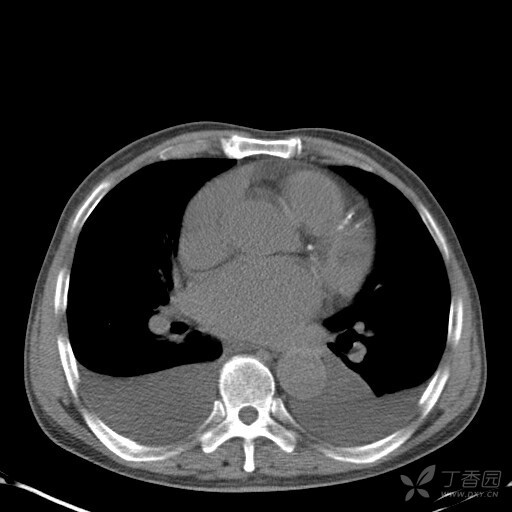

卧位胸片中胸腔积液的探讨 [精华]